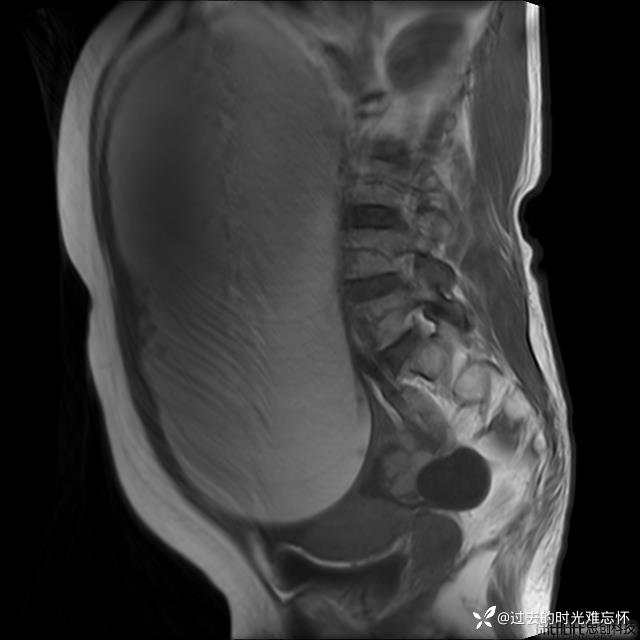

患者性别:女

患者年龄:65岁

主诉: 发现腹部隆起半年余。无其他明显不适。

浆液性囊腺瘤 (22)